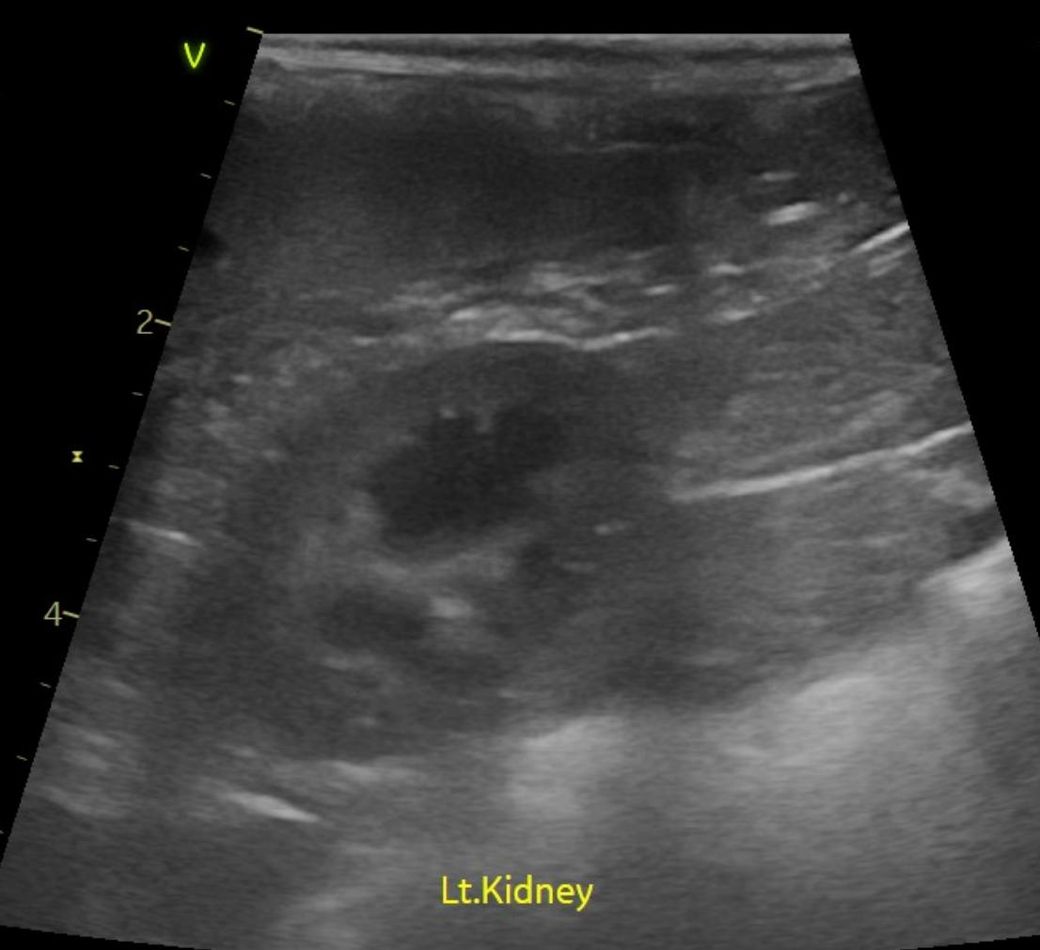

강아지 신장결석 칼슘옥살 스트루바이트 둘중 어느것 같아보이는지요?

강아지 신장결석 칼슘옥살 스트루바이트 둘중 어느것 같아보이는지요? 그냥 보시기에 만약에 판별이 가능하다면 알려주심 정말 감사하겠습니다. 병원만 3곳 다녔고 소변검사에 방광천자 제외하고 전부다 해봤는데 현재 6개월이 넘어갔는데 무슨 결석인지도 모르는 상태고 결석 크기는 신장 양쪽에 점점 커지고 있는 상황이라 이대로는 가만 있을수가 없어서 이렇게나마 질문글 올립니다.. 부디 알려주심 정말 한생명 살리는샘치고 정말 감사하겟습니다.

안녕하세요. 박창민 수의사입니다. 초음파 검사로 결석이 있는지, 위치나 크기, 개수, 형태 같은 정보는 확인할 수 있지만 결석의 정확한 종류나 성분까지는 알 수 없으며, 결석의 성분을 확인하려면 결석을 직접 채취해 분석하거나 소변 검사, X-ray, CT 등의 추가 검사가 필요합니다. 감사합니다.